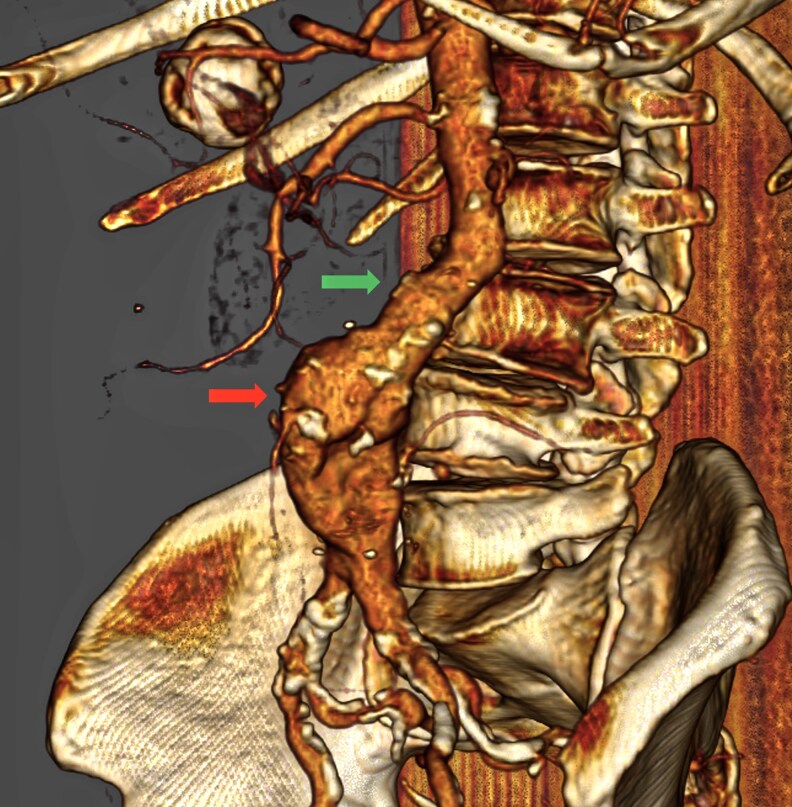

主动脉疾病,包括胸主动脉和腹主动脉的动脉瘤和闭塞性病变,是心血管发病率和死亡率的一个重要来源。本文探讨了现代和新兴的成像方式在主动脉疾病治疗中的作用,并强调了计算机断层血管造影(CTA)、磁共振成像(MRI)和超声造影(CEUS)的关键作用。CTA仍然是评估动脉瘤、夹层和创伤性损伤的基础,提供高空间分辨率、快速获取和详细的解剖评估。MRI,特别是先进的序列,如4D流,提供全面的多参数评估,而不需要辐射暴露,使其成为年轻患者和需要重复成像的理想选择。正电子发射断层扫描(PET),特别是当与CTA或MRI结合使用时,可以表征主动脉壁炎症和感染的代谢特征。超声,特别是超声造影,在腹主动脉瘤(AAA)筛查和血管内动脉瘤修复后(EVAR)监测中仍然是不可或缺的,特别是在肾功能损害患者中。包括混合成像、放射组学和人工智能(AI)在内的新兴技术正在重塑主动脉诊断的格局。这些创新增强了对细微成像特征的检测,自动化测量,并可能实现疾病进展或并发症的预测。

Aortic diseases, including aneurysmal and occlusive pathologies of the thoracic and abdominal aorta, represent a significant source of cardiovascular morbidity and mortality. This narrative review explores the role of modern and emerging imaging modalities in the management of aortic disease and highlights the pivotal roles of computed tomography angiography (CTA), magnetic resonance imaging (MRI), and contrast-enhanced ultrasound (CEUS). CTA remains the cornerstone for evaluating aneurysms, dissections, and traumatic injuries, offering high spatial resolution, rapid acquisition, and detailed anatomical assessment. MRI, particularly with advanced sequences such as 4D flow, provides comprehensive multiparametric evaluation without radiation exposure, making it ideal for younger patients and those requiring repeat imaging. Positron emission tomography (PET), especially when integrated with CTA or MRI, enables metabolic characterization of inflammation and infection in aortic walls. Ultrasound, particularly CEUS, remains indispensable in abdominal aortic aneurysm (AAA) screening and post-endovascular aortic aneurysm repair (EVAR) surveillance, especially in patients with renal impairment. Emerging technologies, including hybrid imaging, radiomics, and artificial intelligence (AI) are reshaping the landscape of aortic diagnostics. These innovations enhance detection of subtle imaging features, automate measurements, and may enable prediction of disease progression or complications.